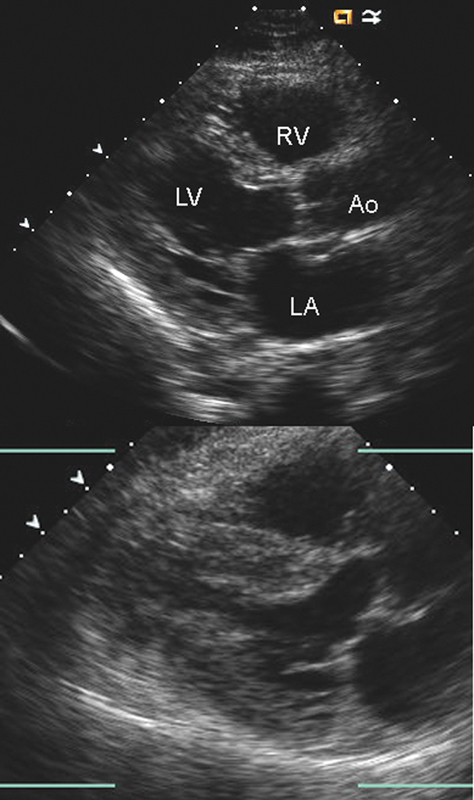

فحوصات تشخيصية لبعض امراض القلب والشرايين التاجية